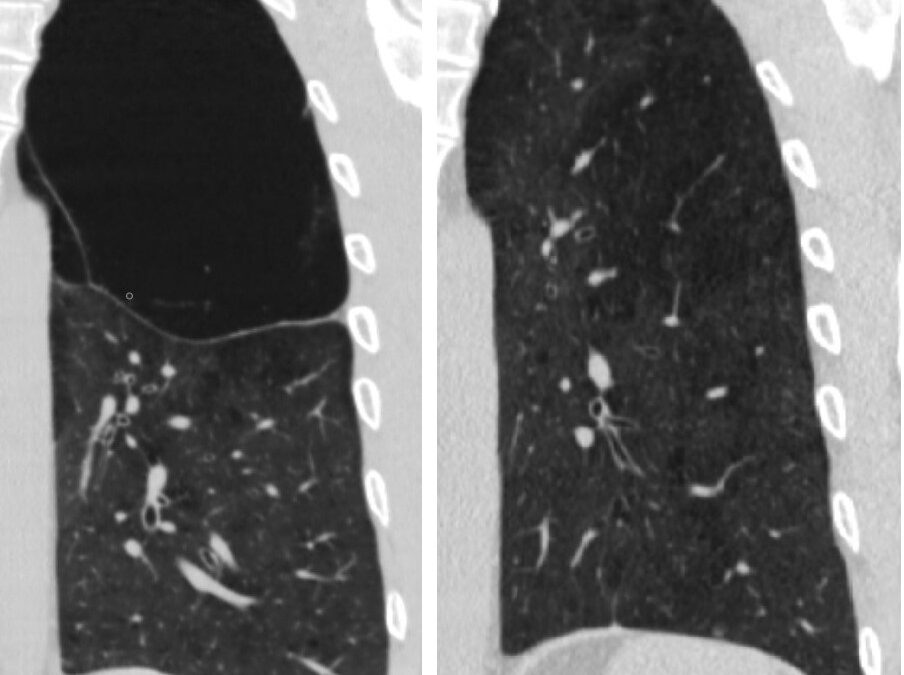

ფილტვის მოცულობის ბრონქოსკოპიული შემცირება ბულოზური ემფიზემის შემთხვევაში

პაციენტი 42 წ მამაკაცი. აქტიური მწეველი. თავს ავად გრძნობს რამოდენიმე თვეა. ჩივილები: ძლიერი ქოშინი ფიზიკურ დატვირთვაზე, ჰაერის უკმარისობა, საერთო სისუსტე. გულმკერდის კტ კვლევით – ორივე ფილტვის ზედა წილებში გაიშვიათებული ფილტვის ქსოვილი, გიგანტური ბულები 10-14...